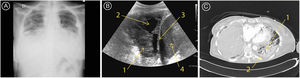

Consulta de nuevo por insuficiencia respiratoria aguda grave, con sospecha de broncoaspiración tras una ingesta alimentaria. La paciente no presentaba datos de infección clínicos ni analíticos, sin reactantes de fase aguda ni aislamiento microbiológico. La imagen por radiografía de tórax (A) muestra un aumento de densidad en la base izquierda que indica derrame pleural y la paciente ingresa en UCI para drenaje del derrame como en anteriores ocasiones. Sin embargo, por ecografía pulmonar se objetiva un patrón C de condensación alveolar (B.1.) con hipoecogenicidades que se corresponden con cavitaciones (B.2.), compatible con una neumonía cavitada. Dicha imagen muestra la base pulmonar izquierda, donde la marca B.3. corresponde al diafragma y la B.4. al bazo. La tomografía computarizada confirma el diagnóstico, objetivando la condensación basal izquierda (C.1.) y una pequeña lámina de derrame pleural (C.2.). figura 1